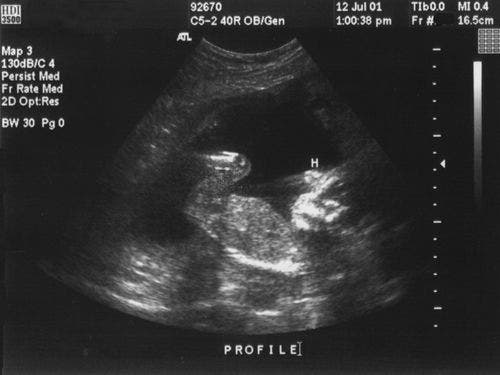

Die Phasenmodulierung wiederum ist eine Methode, um diese Interaktionen durch die Zeitversetzung der von zwei oder mehr Quellen erzeugten Wellenfronten zu steuern. Mit ihr kann die Energie einer Wellenfront gebeugt, gesteuert oder fokussiert werden. In den 1960er Jahren begannen Forscher, Ultraschall-Phased-Array-Systeme zu entwickeln, die mit mehreren Punktschwingern als Impulsquelle die Schallbündel mittels dieser Interferenzmuster steuern konnten. In den frühen 1970er Jahren erschienen zuerst Phased-Array-Geräte für die medizinische Diagnose im Handel, die anhand von gesteuerten Schallbündeln Querschnittsbilder des menschlichen Körpers erstellten.

Anfangs war der Einsatz von Ultraschallgruppenstrahlergeräten auf die Medizin beschränkt, da Beschaffenheit und Aufbau des menschlichen Körpers vorhersehbar sind, was die Geräteauslegung und Bildanalyse verhältnismäßig einfach gestaltet. Industrielle Anwendungsbereiche stellen dagegen wegen der großen Verschiedenheit der akustischen Eigenschaften von Metallen, Verbundwerkstoffen, Keramik, Kunststoffen und Glasfaser und auch wegen der verschiedenen Dicken und Geometrien eine weit größere Schwierigkeit dar. Die ersten industriellen Phased-Array-Systeme, die in den 1980er Jahren eingeführt wurden, waren extrem groß und mussten zur Datenbearbeitung und -darstellung an einen Rechner angeschlossen werden. Diese Geräte wurden insbesondere zur Prüfung von Stromerzeugungsanlagen während des Betriebs eingesetzt. Diese Technologie wurde vor allem für die Atomindustrie weiterentwickelt, bei der die Überwachung von kritischen Elementen den Einsatz von Spitzentechnologien zur Verbesserung der Wahrscheinlichkeit der Fehlererkennung rechtfertigte. Andere Anwendungsbereiche in den ersten Jahren waren die Prüfung von langen geschmiedeten Wellen und die Komponenten von Niederdruckturbinen.